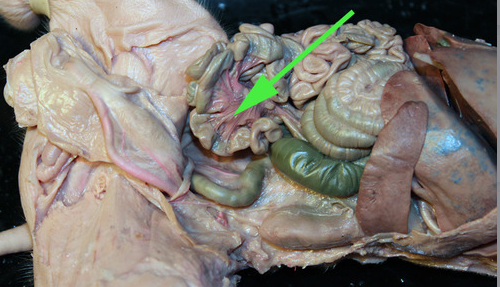

The pink vessels marked by the arrow are branches off the

mesenteric artery.

Areas of diffuse lymphatic tissue are found in the walls of the structures marked by the green arrows. They are called the///small intestine

The diffuse lymphatic tissue found in the structure marked by the green arrow is called peyer's PATCH

The green arrow is indicating the peyer's patch in this area of the small intestine. It is made up of a dense accumulation of what kind of cells?//lymphocytes